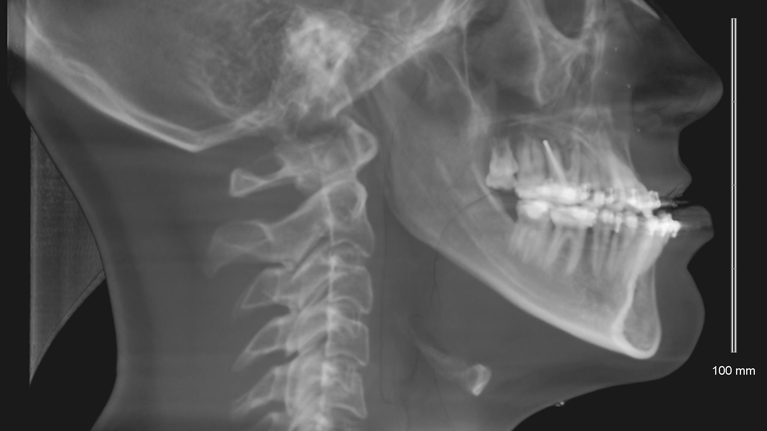

Du skal være færdigudvokset før operationen. Dette undersøger vi vha. et røntgenbillede af din hånd. Du får taget røntgenbilledet enten hos bøjletandlægen eller på Kæbekirurgisk Ambulatorium.